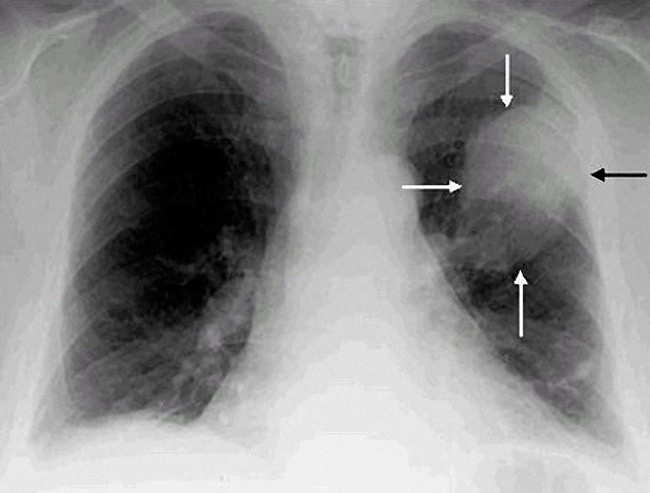

Бронхолегочное кровотечение было связано с 16-кратным повышением риска нового диагноза бронхолегочного рака (ОР, 15,8; 95% ДИ, 6,0-41,3).

Выводы? Если вы принимаете антикоагулянт по поводу фибрилляции предсердий (или по любому иному поводу) и у вас развилось кровотечение из желудочно-кишечного тракта, из мочевыводящих путей или легочное кровотечение - надо подойти к делу самым серьезным образом и обследоваться на рак. Вероятность его найти серьёзная. Лучше его обнаружить раньше и прооперировать/пролечить, чем дожидаться тех времен, когда он сам себя обнаружит явными симптомами, но тогда уже скорее всего будет поздно.

Причем обследоваться надо не лабораторные онкомаркеры сдавая, а выполняя диагностику методами медицинской визуализации. Однако самое лучшее - сразу обратиться к врачу соответствующего профиля (торакальному хирургу или пульмонологу, урологу или гастроэнтерологу). Со всеми жалобами и данными о кровотечении. Они и проведут вас наилучшим и наикратчайшим путем к правильному диагнозу.